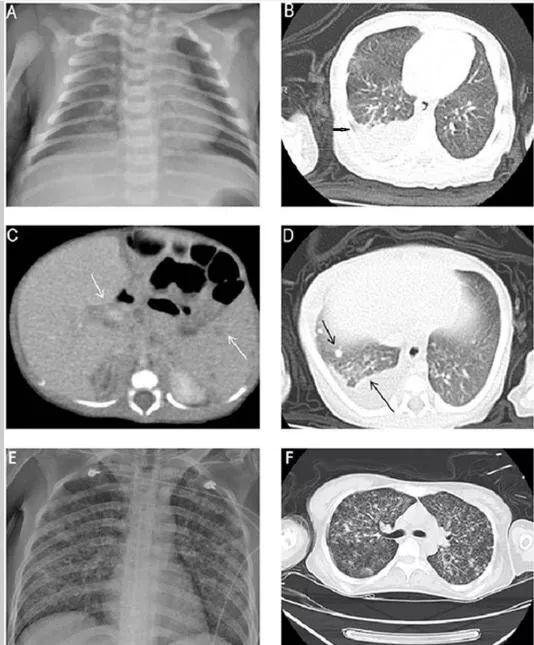

出生后17天:X线胸片右肺野浸润增加(图1A),胸部CT显示婴儿右下叶有大量的右侧胸腔积液和轻微的炎性改变(图1B)。当时,建议进行胸腔积液引流,但他的父母拒绝了。

出生后20天:经父母同意,进行洗胃,洗胃液的三种耐酸染色发现少量的耐酸杆菌。重复进行胸部和腹部CT检查,显示右上肺有斑片状实变,双肺有多个新结节,中度胸腔积液,脾脏和肝门区有多个低密度结节,无肝脏肿大(图1C,D)。随后,进行猪尾导管置入胸腔积液引流术。胸水分析结果显示,白细胞总数为10800/μl,中性粒细胞占6%,淋巴细胞占57%,间皮细胞占37%;总蛋白水平为4.6g/dl,乳酸脱氢酶水平为250IU/L,葡萄糖水平为164mg/dl。怀疑是结核感染。给予异烟肼(15mg/kg/d)、利福平(15mg/kg/d)和吡嗪酰胺(20mg/kg/d)。开始抗结核治疗后,新生儿的症状和体征逐渐消失。

新生儿的母亲是33岁,孕1产1。B组链球菌检测呈阴性。她一直健康,既往没有病史和肺结核接触史;然而,她在分娩后1周出现轻度干咳,出现持续性全身无力,并在产后24天因精神状态改变而住进了我们的ICU。实验室检查显示白细胞增多、血小板减少、凝血障碍、急性肝功能衰竭和急性肾功能衰竭。HIV血清学检测呈阴性。胸片显示粟粒样结核(图1E)。胸部CT显示弥漫性小叶间和小叶内间隔增厚呈毛玻璃样(图1F)。由于当时新生儿高度怀疑有肺结核感染,故对其痰进行抗酸染色和肺结核聚合酶链反应(PCR)。两项检测均呈强阳性。这位母亲立即接受了抗结核治疗,但在住院3天后死亡。痰培养证实结核分枝杆菌感染。